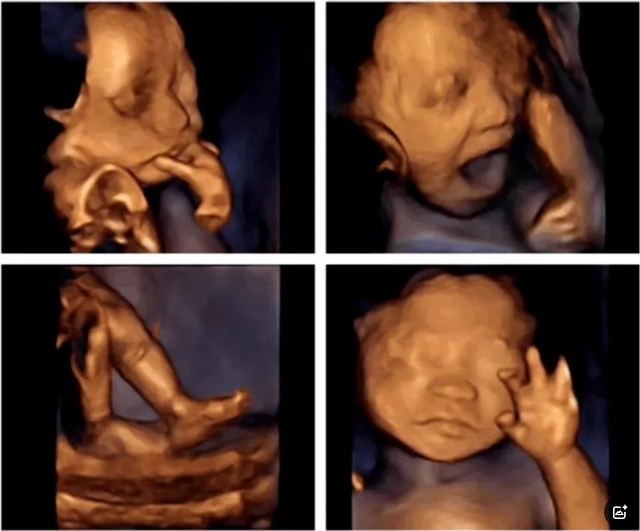

可以检查到胎宝宝在宫内是否缺氧,肢体运动、胎儿的吞咽动作等,能够很好地看到胎儿在孕妈妈体内的活动状况,说不定还可能看见宝宝做鬼脸、伸舌头哦。